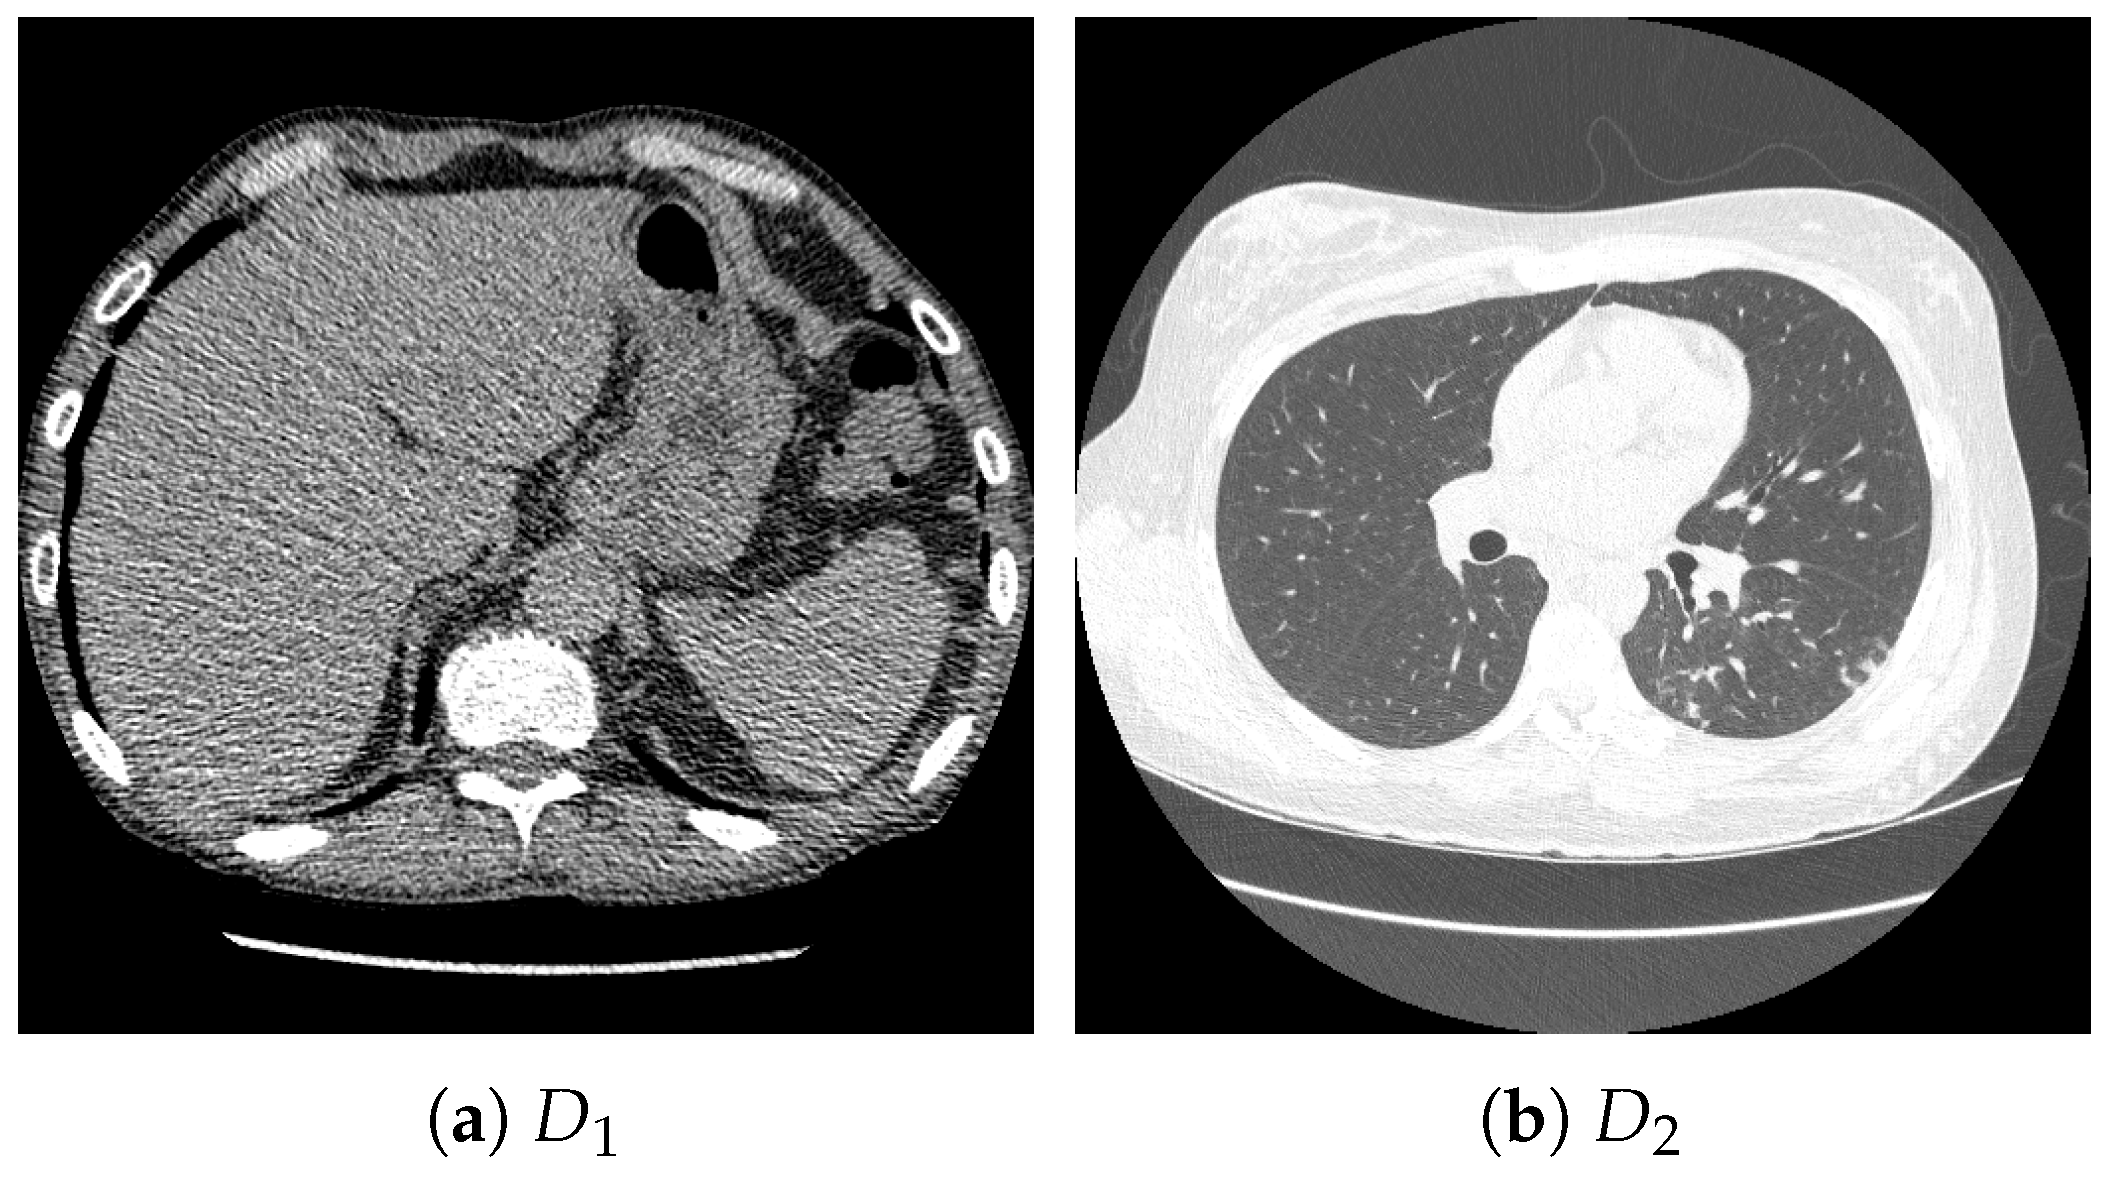

For pretraining, we utilized a subset of the J-MID (https://www.radiology.jp/j-mid/ (accessed on 6 April 2025)) database, which contains large-scale CT scans from Japanese medical institutions, and the RICORD dataset [58], an open dataset that was developed collaboratively by the Radiological Society of North America and international partners and contains chest CT scans collected from four countries. Each dataset was constructed with two domains based on mediastinal and lung window settings in chest CT images. Both domains are denoted as and , and the labels are not used during pretraining. Specifically, for the J-MID subset, (the mediastinal window) contains 31,256 CT images, and (the lung window) contains 26,403 CT images. The RICORD dataset comprises 12,897 (mediastinal window) images and 11,668 (lung window) images for pretraining. For the J-MID dataset, was generated using a window level (WL) of HU and a window width (WW) of HU, whereas was generated using a WL of HU and a WW of HU. For the RICORD dataset, was generated with a WL of HU and a WW of HU, while was generated with a WL of HU and a WW of HU. These parameter ranges were selected to cover clinically standard lung and mediastinal window settings while accommodating inter-scan variability in DICOM metadata. The corresponding images for each example are shown in Figure 2 and Figure 3. For fine-tuning and evaluation, we utilized two public datasets: the SARS-CoV-2 CT-Scan Dataset [59] and the Chest CT-Scan Images Dataset (https://www.kaggle.com/datasets/mohamedhanyyy/chest-ctscan-images (accessed on 6 April 2025)). Both datasets were used for the coronavirus disease 2019 (COVID-19) and chest cancer classification tasks, respectively. The data breakdown is as follows: the SARS-CoV-2 CT-Scan Dataset comprises 1589 training, 397 validation, and 495 test images, labeled into two (COVID-19 and Normal) classes. The Chest CT-Scan Images Dataset comprises 490 training, 123 validation, and 315 test images labeled into four (adenocarcinoma, large-cell carcinoma, squamous-cell carcinoma, and normal) classes. COVID-19 classification and lung cancer classification were selected as downstream tasks because chest CT is widely used in clinical practice for diagnosing both COVID-19 and lung cancer, allowing for an evaluation that closely reflects real-world clinical scenarios. Accordingly, to ensure reproducibility and enable fair comparisons with prior studies, we prioritized the use of publicly available datasets. The corresponding images for each example are shown in Figure 4 and Figure 5.

Figure 3.

Examples of chest CT images on the subset from the RICORD dataset: (a) and (b) .